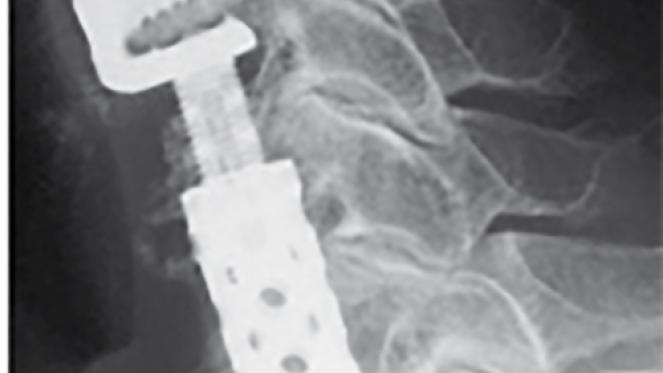

In manchen Fällen  (ausgedehnte Retrospondylose mit zervikaler Spinalkanalstenose oder auch bei einer Ossifikation des hinteren Längsbandes (OPLL)) ist eine Entfernung ganzer Wirbelkörper erforderlich (Korporektomie). Diese werden dann durch Platzhalter aus Titan, Kunststoff oder (heute seltener) aus körpereigenem Knochen ersetzt.